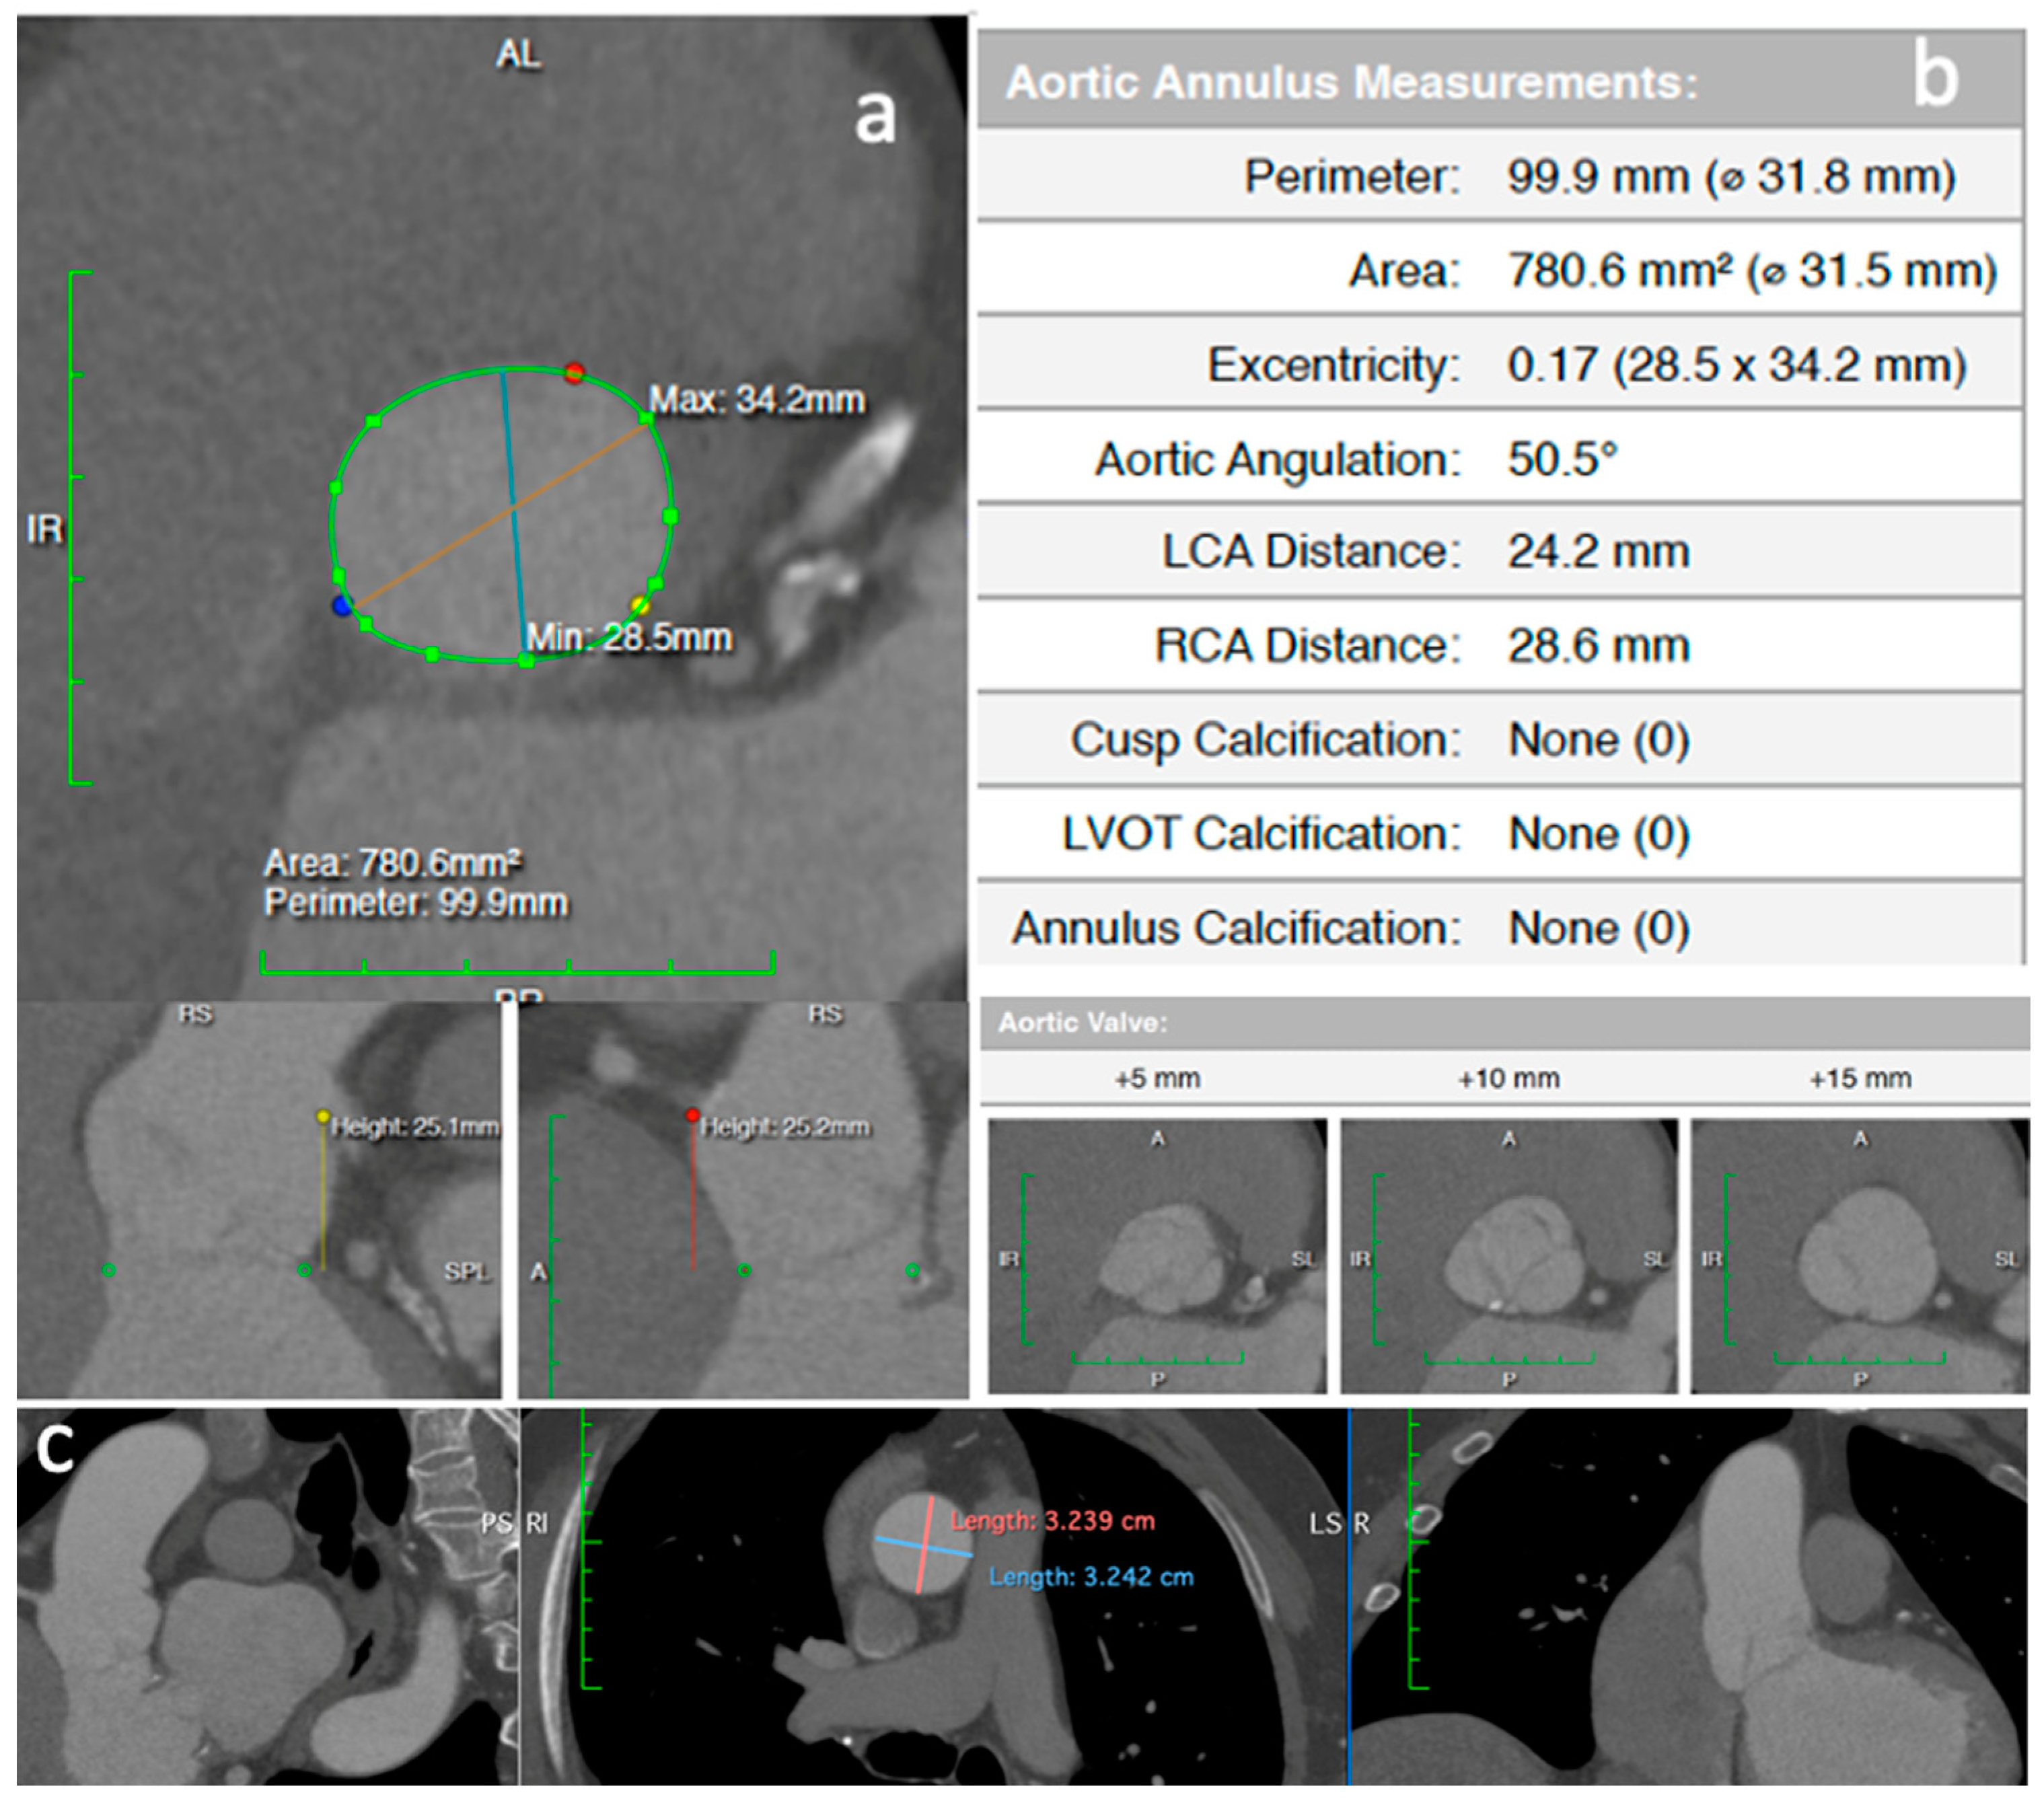

2. Clinical Vignette